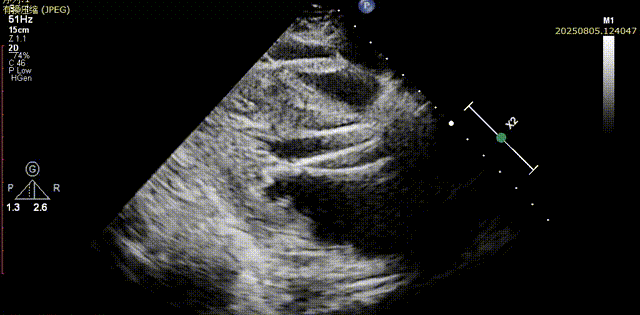

瓣膜脱钩

脱钩后输送器部分回收,瓣膜无位移及形变,确认瓣膜完全脱钩,回撤输送系统及导丝,超声再次评估,瓣膜位置及形态良好,无明显瓣周漏,峰值流速2.44m/s,平均压差13mmHg,患者未诉不适,入路缝合后返回病房

胸骨旁长轴评估